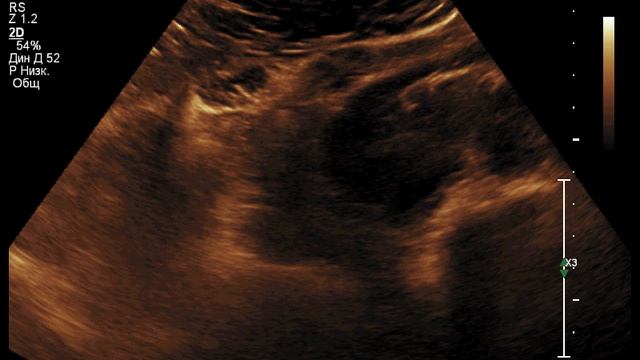

Подковообразная почка — порок развития органов мочевой системы, характеризующийся сращением почек друг с другом в области нижнего полюса., видео от 2024-10-12 загрузил на rutube uzi_olga...